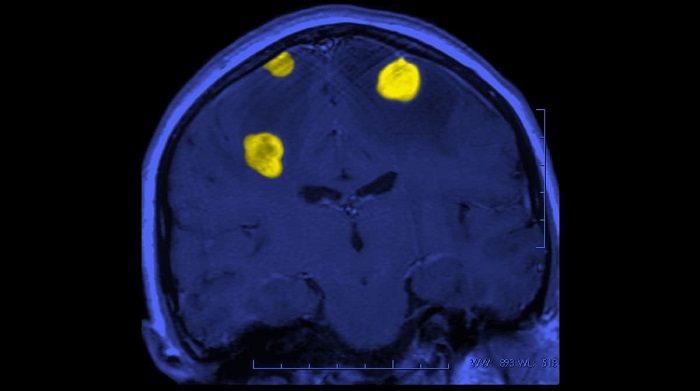

Thuốc điều trị bệnh Parkinson đã ngừng sử dụng có thể có tác dụng chống ung thư não (11/12/2023)

Các nhà nghiên cứu đã phát hiện ra một loại thuốc hiện đã ngừng sử dụng để điều trị các triệu chứng của bệnh Parkinson có thể có hiệu quả trong điều trị ung thư vú di căn và di căn não. Loại thuốc được tái sử dụng này có tiềm năng trở thành một liệu pháp mới trong cuộc chiến chống lại bệnh ung thư.